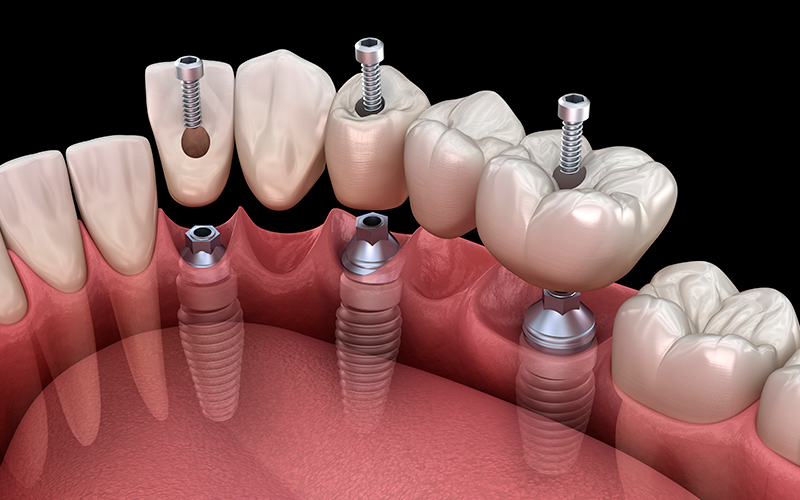

¿Qué es un implante dental?

Un implante dental es una pequeña pieza de titanio que se coloca en el hueso de la mandíbula para reemplazar una pieza dental perdida. Imagina que tienes un diente que ya no puedes salvar; con un implante, podemos poner uno nuevo que se ve y funciona como el original, devolviéndote la capacidad de masticar bien, sonreír con confianza y hablar sin temor.